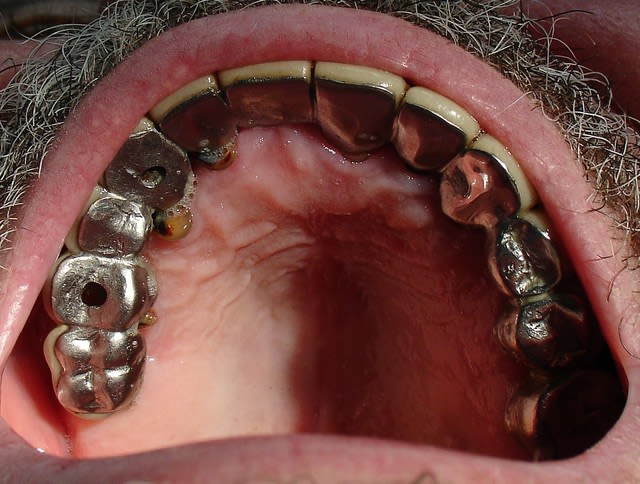

Voici les premieres photos. Peut être verra t'on une différence avec le cas de Jeff.

> je dirai que seulement

> 2/3 dents semblaient conservables 26 et 23 et la Pm intercalée.

On sait maintenant que 2 ou 3 dents sont peut être conservables.

On n'a plus qu'à connaître l'état des dents mandibulaires, et on pourra encore aller plus loin.